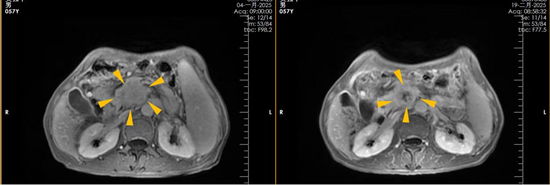

治疗前(左)与治疗后(右)对比图

最令人振奋的是,复查提示肿瘤得到有效控制,肿瘤标志物显著下降。对于经历过失望和痛苦的家庭来说,这份结果无疑带来了久违的希望。